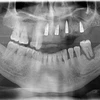

Implant Treatment